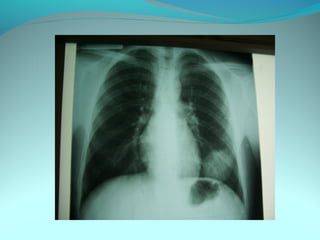

Cliché normal